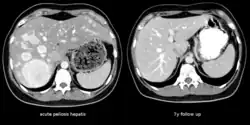

The CT scan of a patient with peliosis hepatis (left): The follow-up CT (right) after 7 years shows full remission.